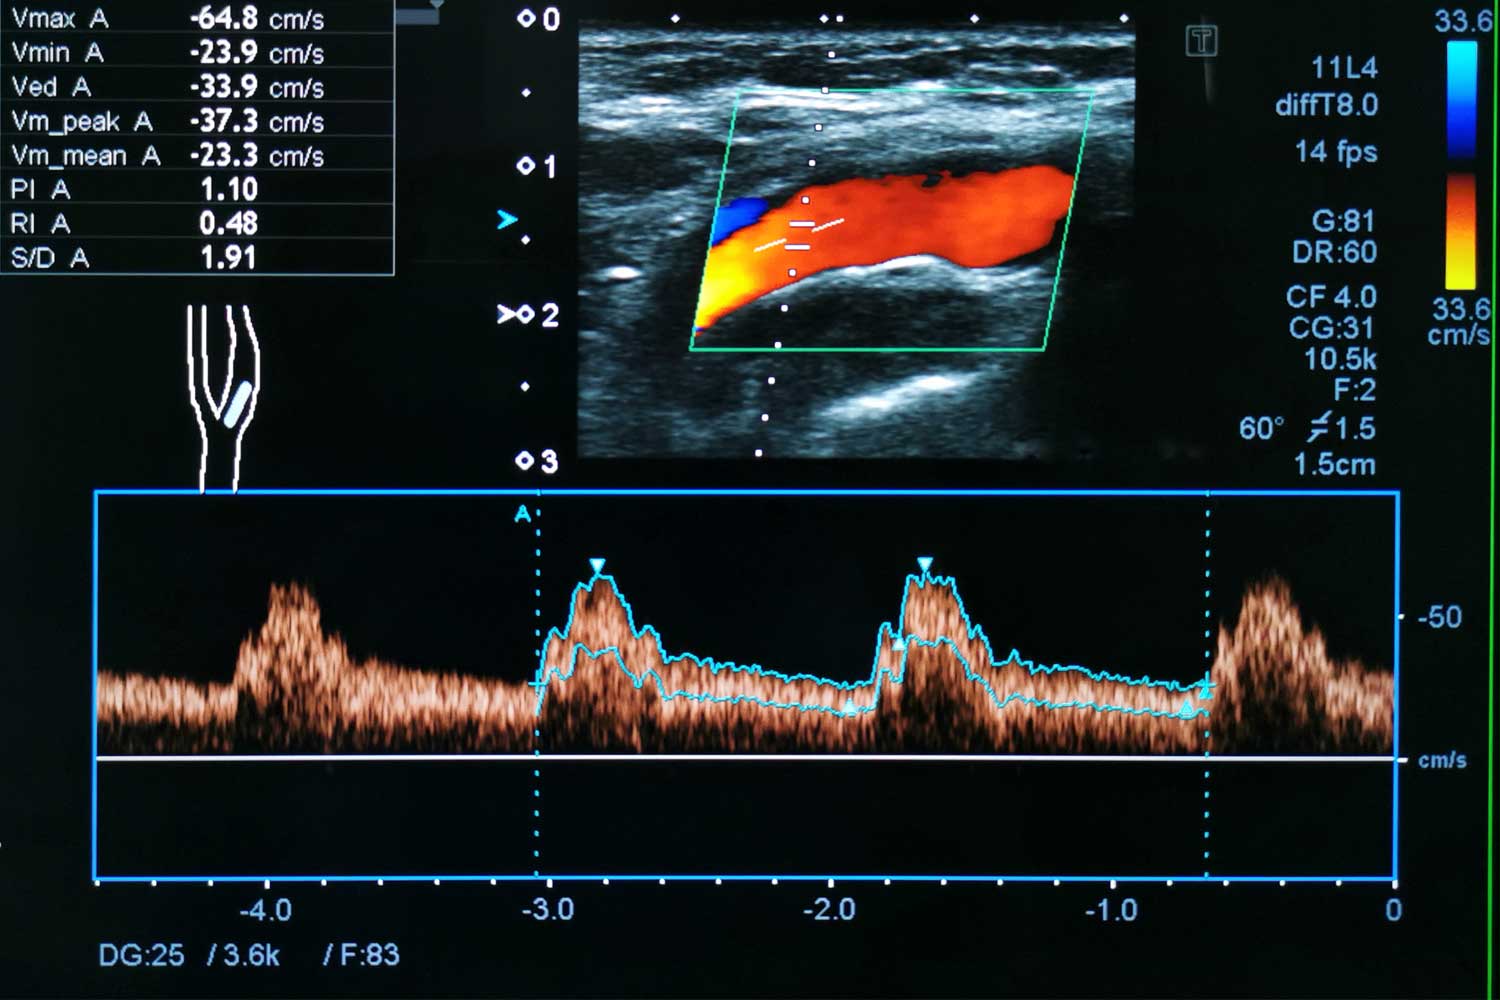

Doppler ultrasound measures the speed and direction of blood flow through the carotid arteries. When an artery is narrowed, blood speeds up as it passes through the tight area — similar to how water flows faster through a partially closed garden hose. By measuring these velocities, the sonographer and radiologist can estimate the degree of narrowing (stenosis) with remarkable accuracy.

Color Doppler adds color to the image to visualize flow direction (red for flow toward the transducer, blue for flow away), while spectral Doppler produces a waveform graph of flow velocities at specific points in the artery.

A board-certified radiologist reviews the images and Doppler measurements and grades the degree of carotid stenosis using standardized velocity criteria: